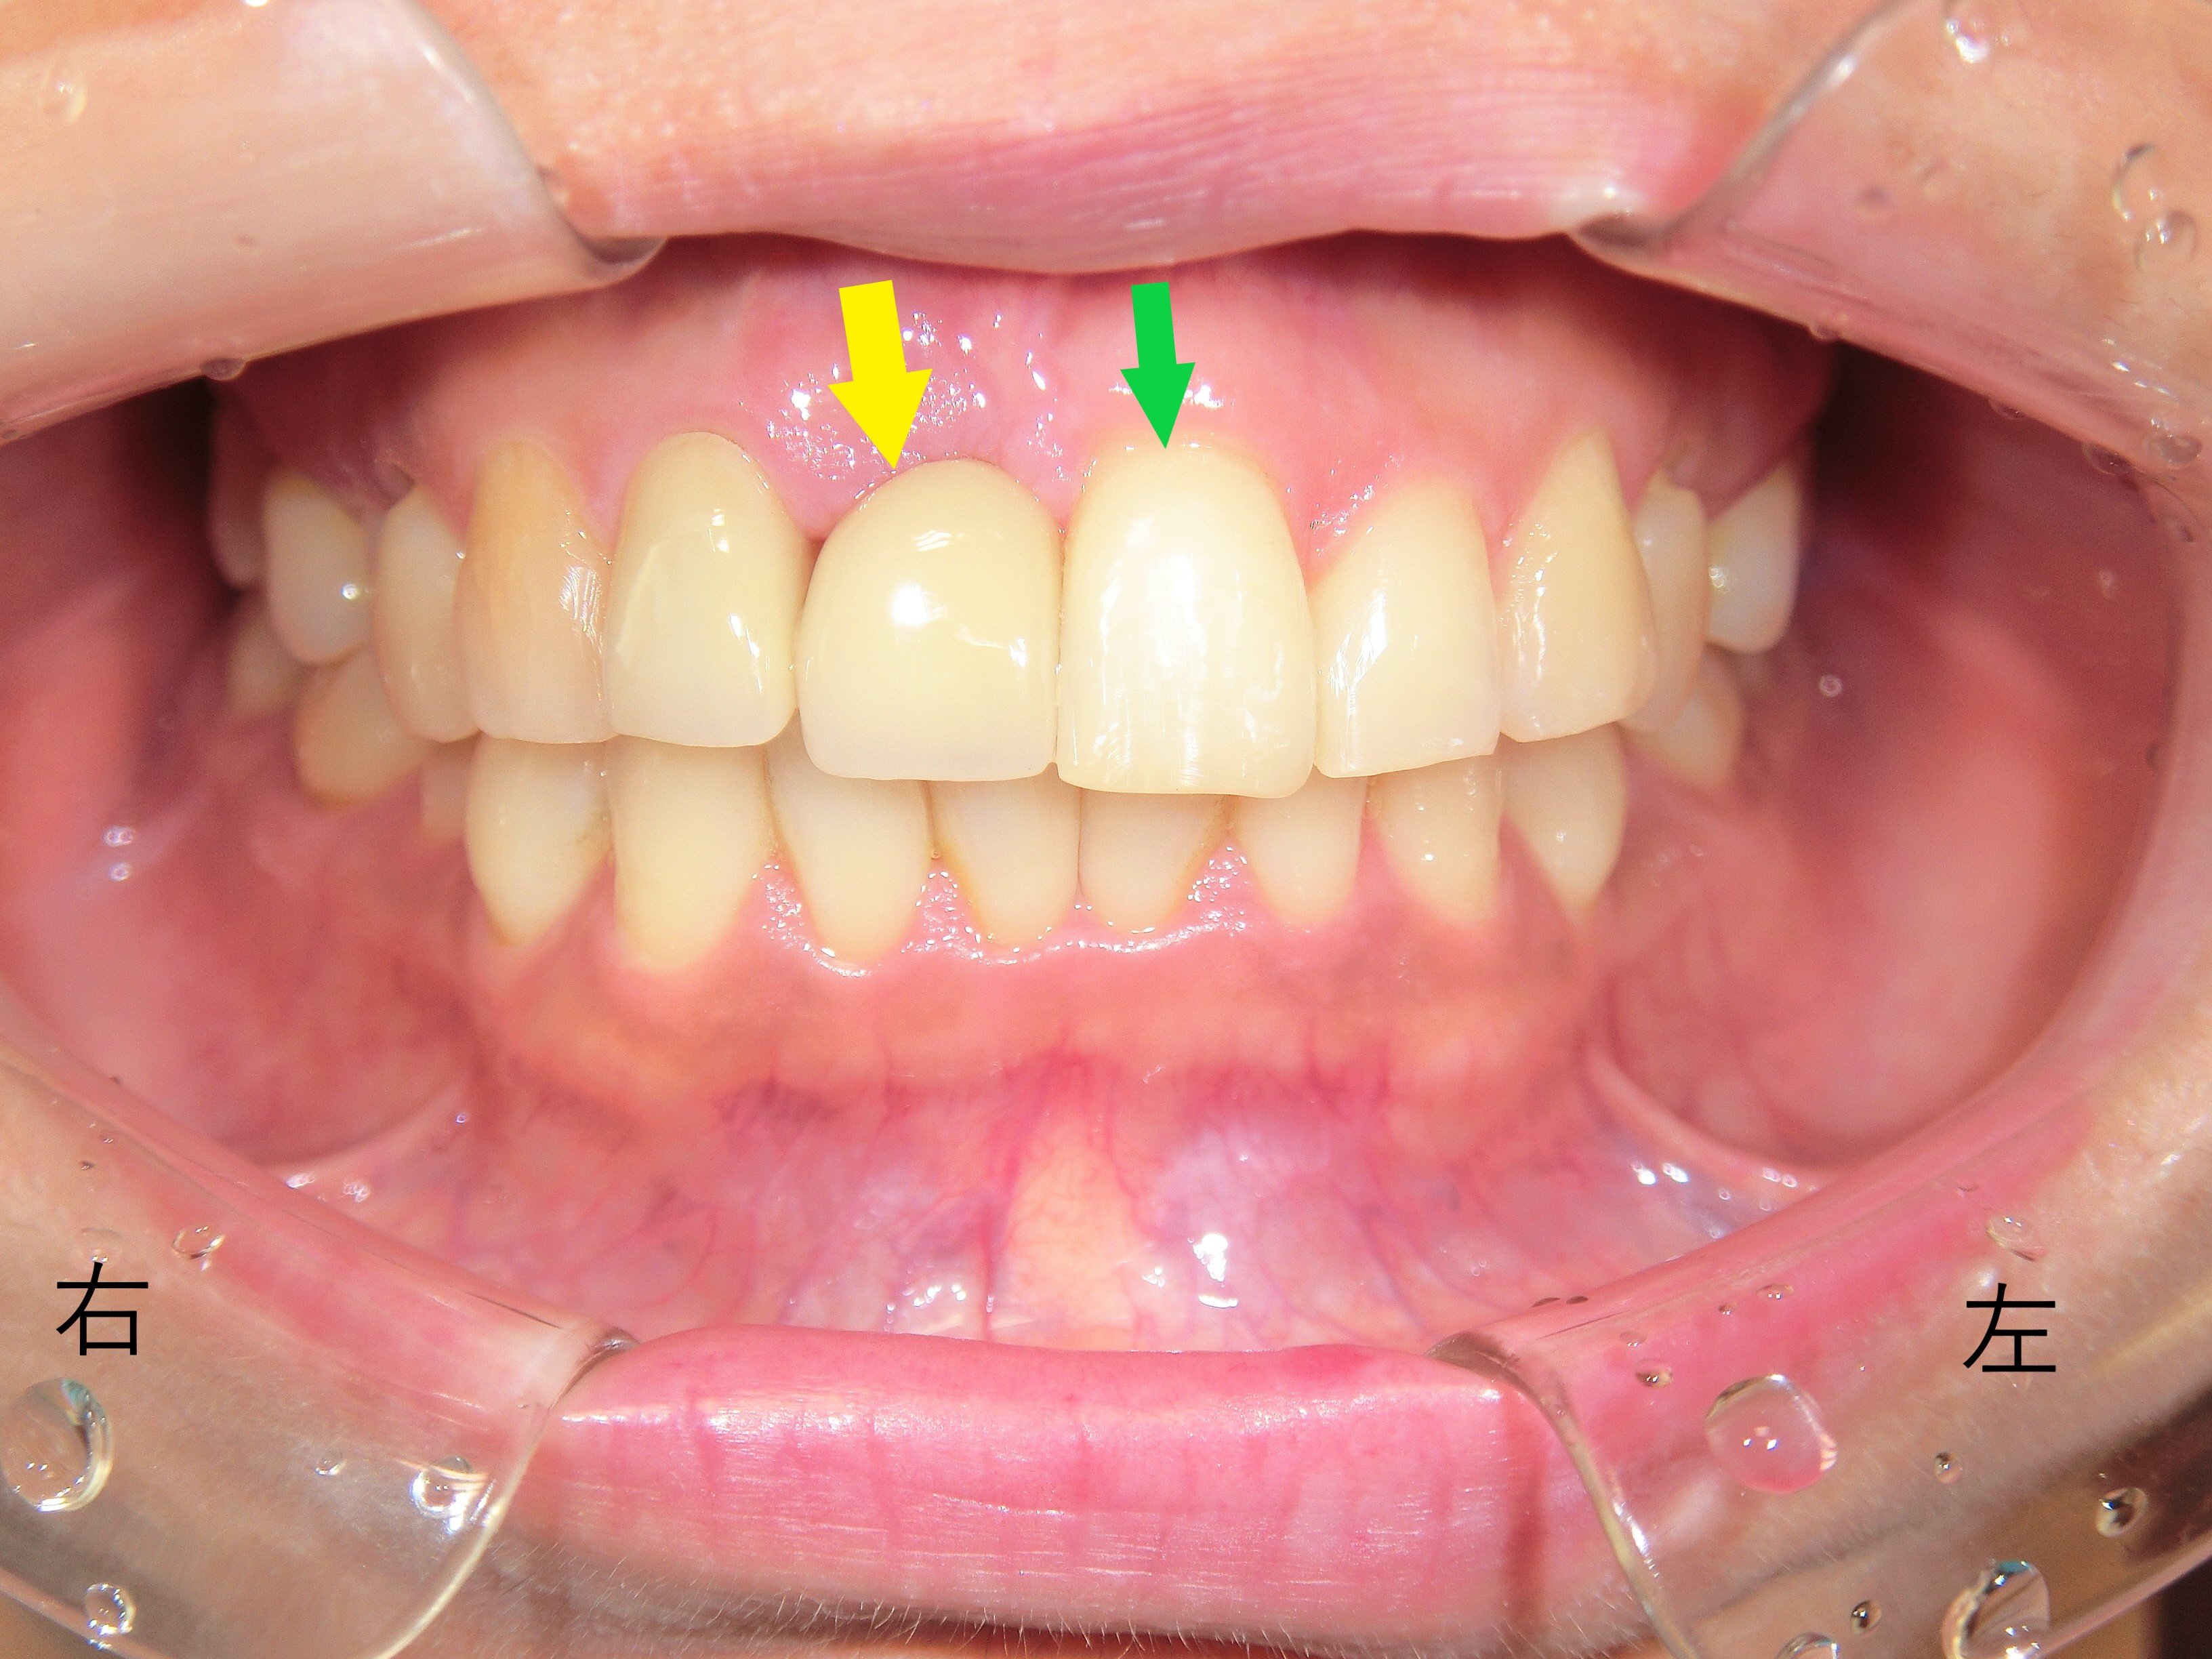

【治療終了時の正面写真】

左上前歯(緑色矢印)が内側に移動し、右上前歯(黄色矢印)と左右対称の位置関係を実現しました。患者様にもご満足いただけました。

ただし、繰り返しになりますが、プチ矯正治療は一般的に前歯を内側に大きく移動させることを目的とした治療ではありません。通常は前歯の重なりを整えたり、すき間を閉じたりする範囲に限られます。

今回のように明らかな前方移動が実現できたケースは、あくまで例外的な症例であることをご理解ください。